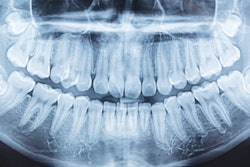

Pearl's Second Opinion dental radiology artificial intelligence (AI) software will soon be available in Australia and New Zealand.

The software has received marketing clearances from Australia's Therapeutic Goods Administration (TGA) and Medsafe, New Zealand's Medicines and Medical Devices Safety Authority, to assist dentists in the radiologic detection of pathologies, according to Pearl.